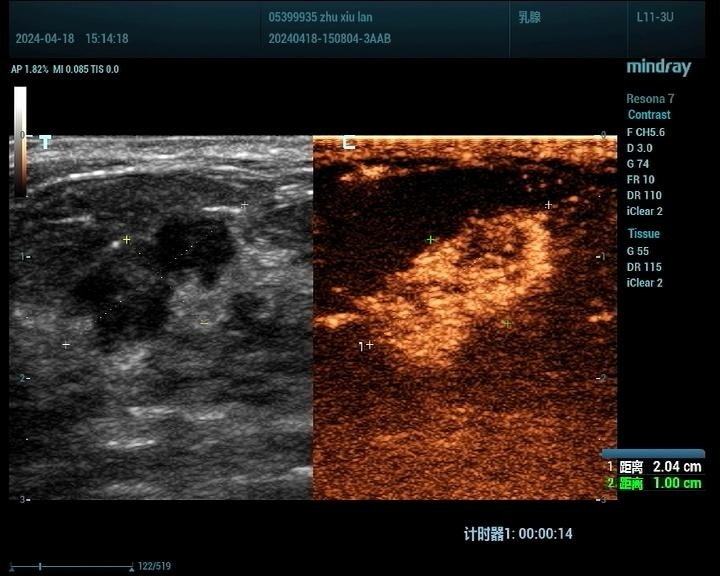

2、乳腺

判断肿瘤的良恶性:通过超声造影,医生可以初步判断乳腺肿瘤的良恶性,为临床治疗提供参考。

明确恶性肿瘤的范围:对于恶性肿瘤,超声造影能够明确其范围,有助于制定手术方案及评估预后。

术后瘢痕与肿瘤的鉴别:乳腺手术后的瘢痕与肿瘤在超声表现上可能存在相似性,超声造影有助于二者的鉴别。

非手术治疗疗效评估:对于非手术治疗的乳腺癌患者,超声造影能够评估其疗效,为治疗方案的调整提供依据。

乳腺癌病例